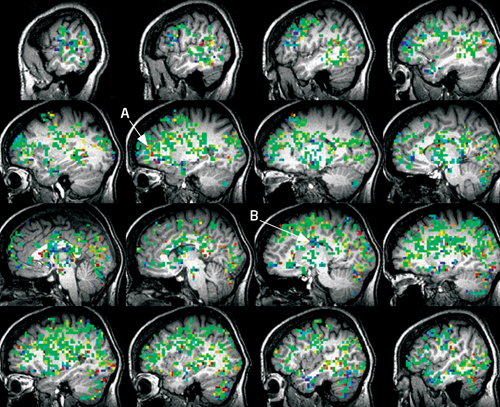

Kayt Sukel performs an intimate act in an fMRI scanner to explore the pathways of pleasure and pain.